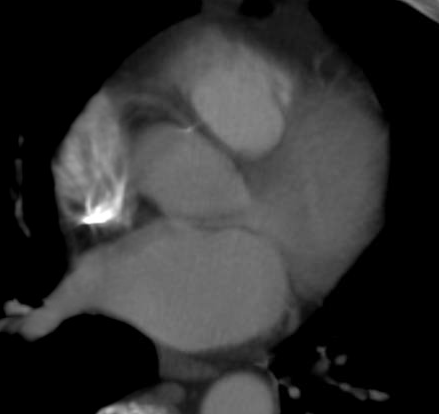

Coronary computed tomography angiography (CCTA) is a noninvasive tool that can be used for identifying myocardial ...

As catheter-based, minimally invasive procedures expand rapidly beyond treatment of the coronary arteries into all areas ...

The next big advancement in cardiac imaging is likely to be computed tomography (CT) perfusion imaging. This enables one ...